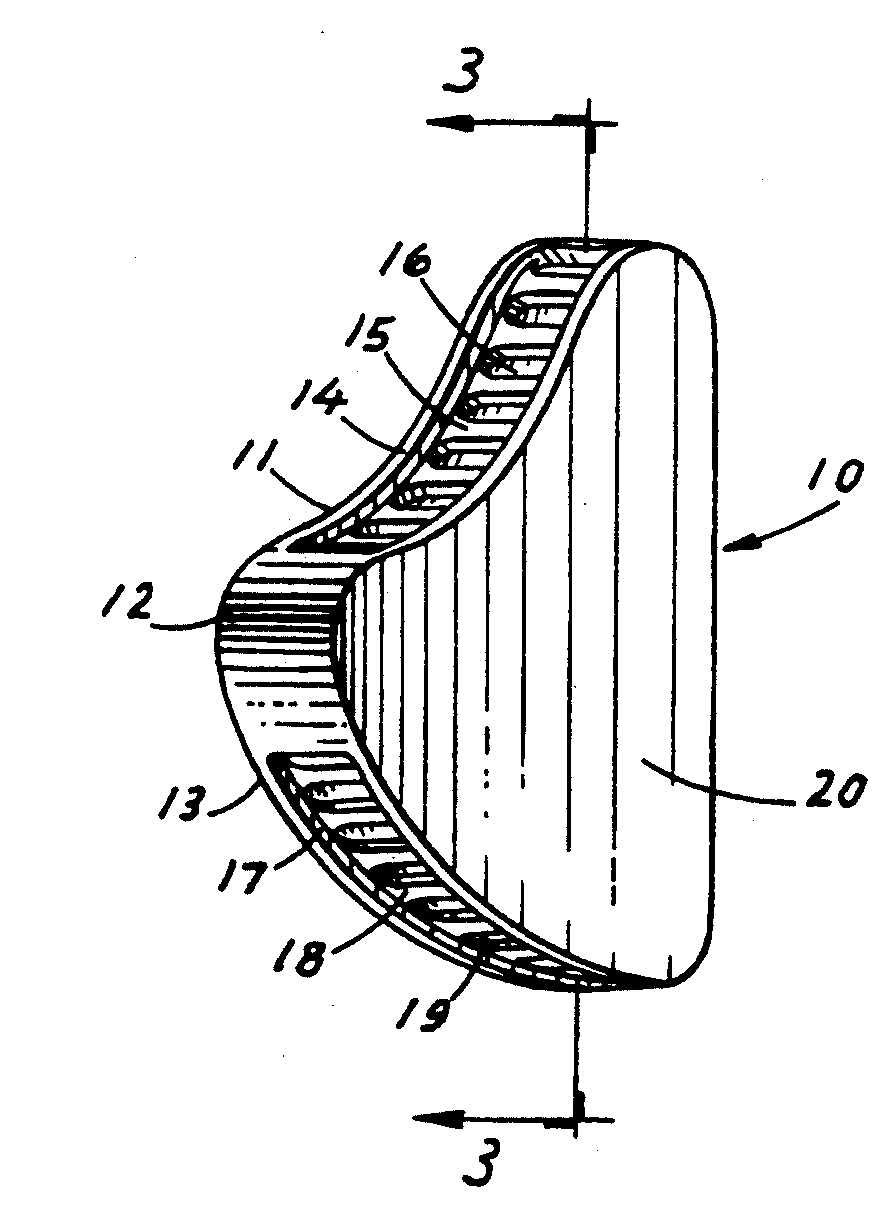

General anesthesia parameters determine procedure time limitations. These include the unique challenges of a safe initial sedation, including consideration of the patients' enclosure situation regarding controlling the patient. Then the veterinarian must consider the inherent physiological risks of general anesthesia. These challenges will determine the opportunities for long, multiple or follow up procedures. They frequently dictate where examination and treatment procedures can be performed also. The dental consultant will also be challenged by these situations to provide diagnosis and treatment.

During the procedure, the dental consultant and anesthesiologist (veterinarian) must be in constant communication. Usually a third individual, veterinarian or veterinary technician is closely involved monitoring the patient and managing IVs etc. The animals' depth of anesthesia must be maintained for its safety and the safety of the operator. Any movements or changes in jaw tension should be continually discussed. Constant communication regarding all aspects of the ongoing procedure will result in safe and successful outcomes.

All the considerations of actual operative treatment choices will be unique to each case. Examination, diagnosis, deciding whether treatment is justified and prioritizing multiple issues presented, must be done promptly when safe general anesthesia is achieved. Again, the opportunity to follow up will be limited, therefore the most definitive treatments must be chosen.